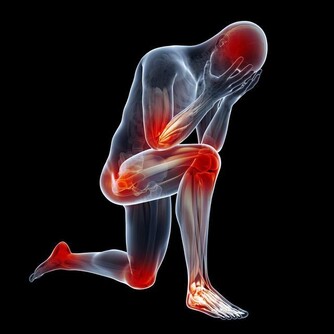

如果動作比較劇烈,或者服用了刺激性的食物,那麼痔瘡會脫垂或腫脹,引起劇痛和便血的症狀。而下列5種習慣會令人更容易患有痔瘡,希望大家能盡量在生活中避免。

因為種種原因,許多人在排便時用勁過猛;如此便會對肛門周圍的血管造成很大壓力,嚴重時會導致血管破裂,廁紙上會有明顯的血跡;長此以往很有可能誘發痔瘡。建議在排便時不要太過用勁,無法排出時,可以輕揉腹部,或是通過調整飲食習慣來促進消化道健康。

鍛煉是一個循序漸進的過程,想要通過深蹲練就翹臀,應該逐漸增加運動量;而不是某天心血來潮,連續做一百個蹲起。突然加大運動量,或是熱身運動不到位,都會對肌肉組織造成不小的壓力,甚至是誘發痔瘡。條件允許時,最好能請專業人士為自己量身打造健身計劃,在專人看護與輔導下使用健身器械。醫生提醒:痔瘡患者的數量龐大,但也不要因為這類疾病比較普遍而不去看醫生。